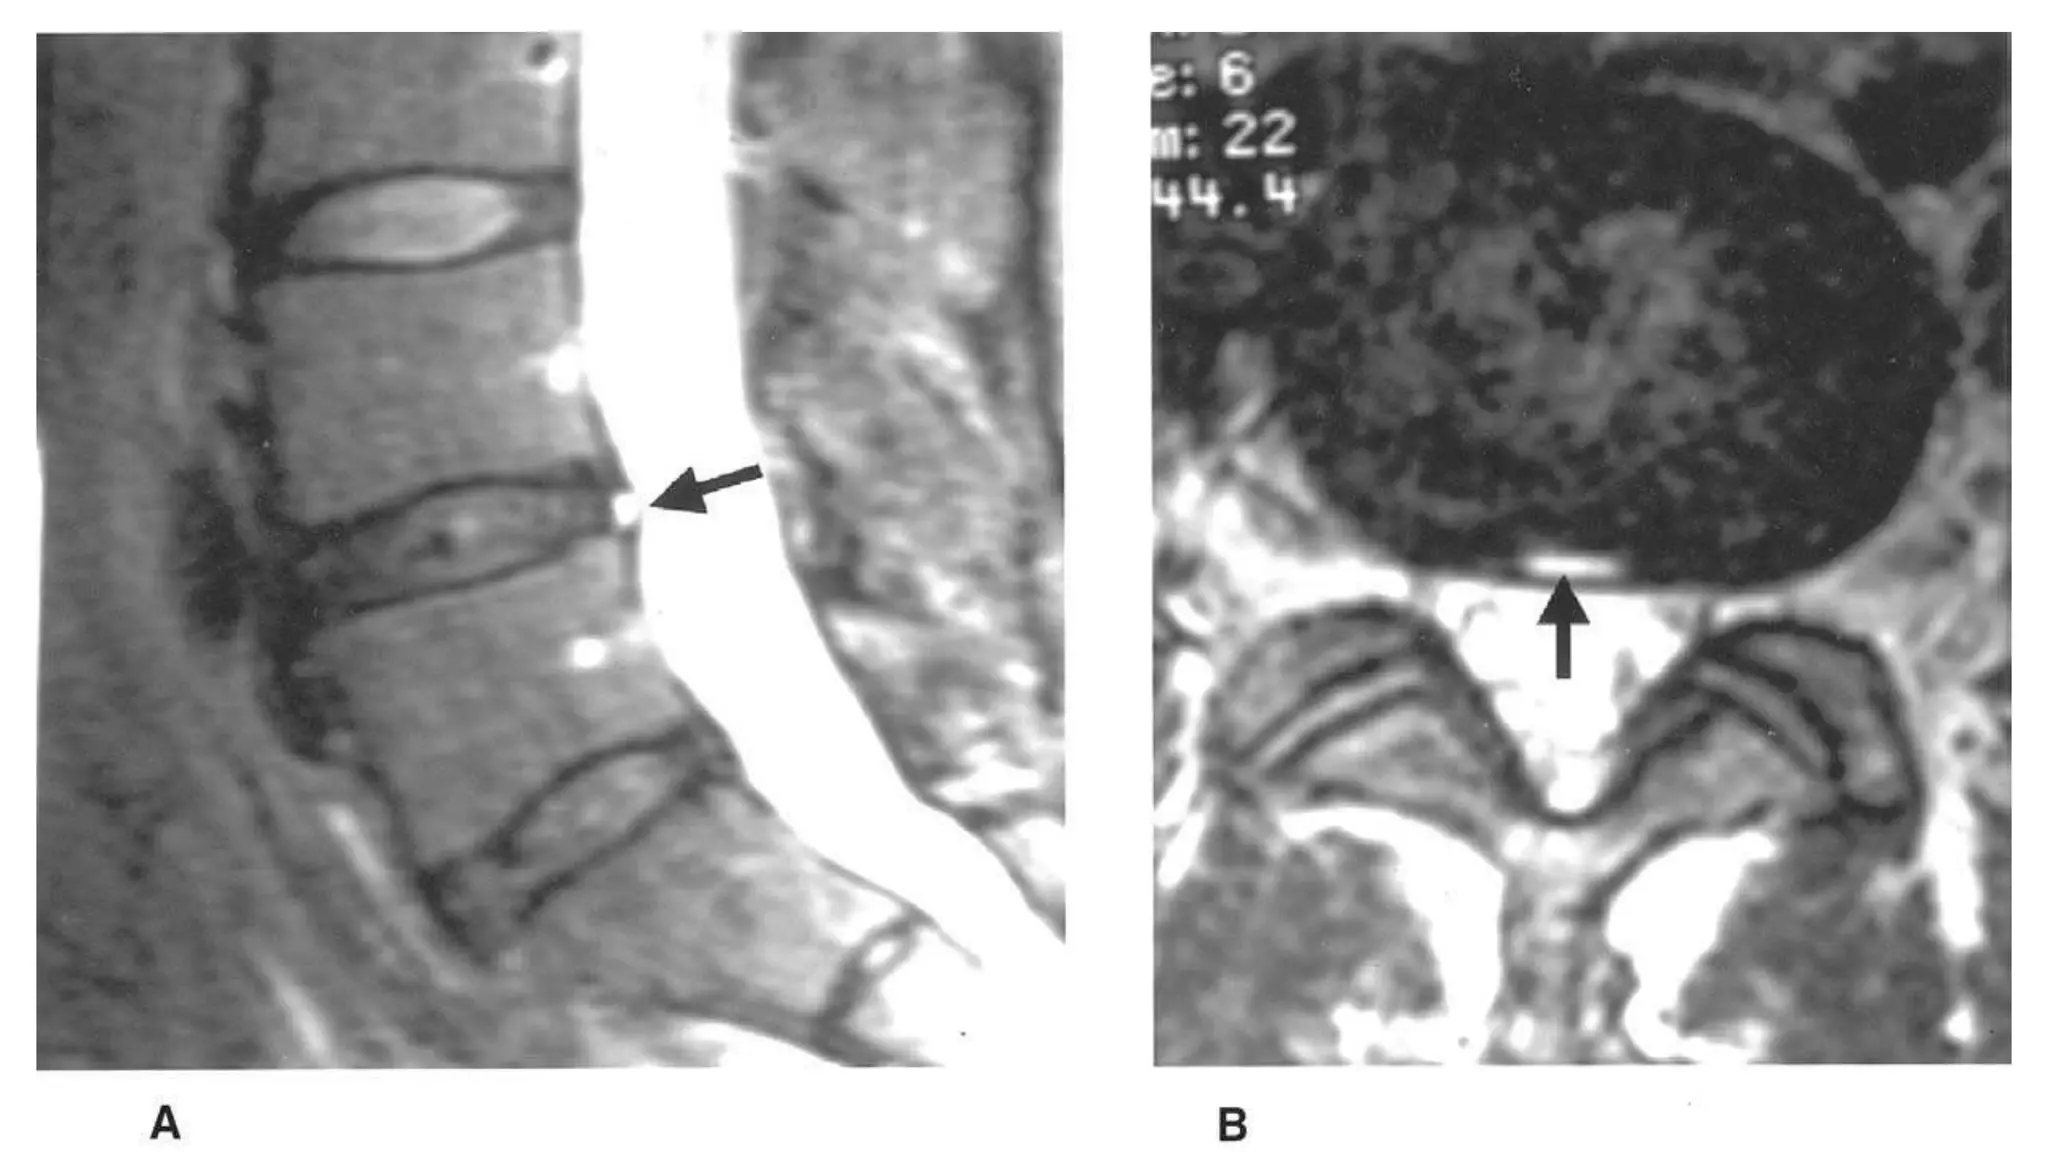

Imaging of lumbar spondylosis PPT